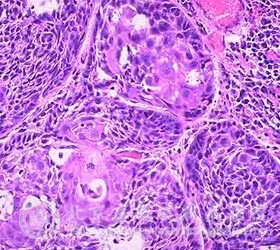

口腔鳞状*癌图片口腔鳞状*癌是发生在口腔的一种癌变,一般发生在下唇的约有38 ,总体上的情况为5年生存率为90 ,一般不会转移.若癌变发生在上唇则更具侵略性,治疗口腔鳞状*癌时,要在唇的大部分呈现恶变前进行,一般需进行外科手术或用激光切去所有被侵及的粘膜。手术过后,建议使用遮光剂并且禁烟。

大约11 的口腔鳞状*癌发生于腭和扁桃体部位.如果在淋巴结未被侵之前治疗,那么患者的5年生存率为68 ,但在淋巴结被侵及后治疗者存活率仅为17 。约有40 的口腔鳞状*癌发生在口底或舌。主要是由于吸烟(特别大量吸烟)和饮酒引起的;吸烟和饮酒对身体造成很大的伤害,容易引发复发及其它的病症。此外,口腔癌病损可出现在红斑或白斑上,在舌上的癌,有淋巴结转移的5年存活率降低至20 ,若无转移则5年的生存率可高一些。对舌癌的治疗主要是外科切除术,或者放射线治疗,或两者联合应用。确诊为淋巴结已受侵害的患者,还需进行颈淋巴清扫术.当有转移发生时,常出现在肺,骨,心脏和心包中,患者因注意预防治疗。